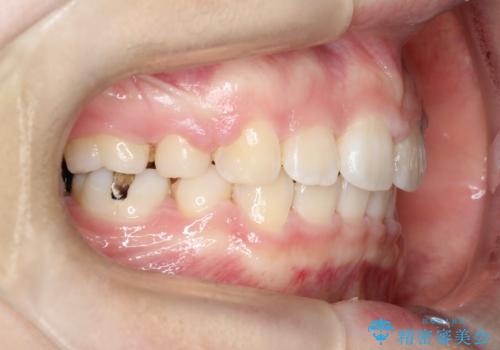

- 口元が出ていることを主訴に来院されました。

上下左右小臼歯を抜歯して審美装置で治療を行いました。

口元もスッキリと変化し、大変満足していただきました。